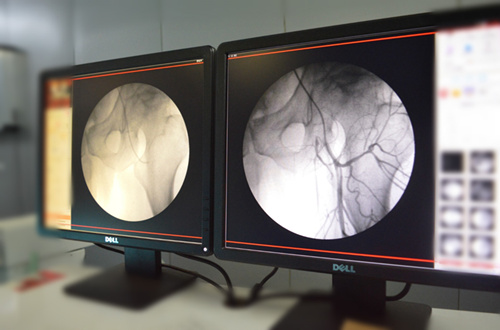

“患病多年,为了能够治好股骨头缺血性坏死跑遍多座城市、多家医院寻医问药,花掉家里几乎所有的积蓄,股骨头缺血性坏死还是没能治好……”这可能是大多数股骨头缺血性坏死患者的心声。对于患者来说,早日康复是最大的心愿,而目前治疗股骨头缺血性坏死的方法纷杂繁多,让很多患者看见了曙光,然而每一次尝试之后,病情仍在反反复复,严重影响患者的工作和生活的同时,也给患者家庭带来了沉重的经济负担,让患者的求医之路变得更加艰难。 股骨头坏死患者为何疼痛反复、久治不愈? 1、从疾病根源看 股骨头坏死的治疗要抓住核心 股骨头坏死又称股骨头缺血性坏死,是一种多病理机制(主要诱因有:酗酒、外伤、激素、髋关节先天性发育不良等)导致股骨头三大动脉血管堵塞而引起股骨头供血障碍,失去营养供应,随着病情发展最终导致骨细胞的缺血与坏死、骨小梁断裂、股骨头塌陷的疾病。其病在骨头上面,而病根在血管上。因此,只有疏通了这三根血管,同时建立起侧支循环,才能彻底解决股骨头坏死的病根难题! >>>你知道自己是哪根血管发生堵塞吗?知道该如何检查吗?点击咨询我们 2、从治疗方式看 你之前接受过何种治疗方法? 目前临床治疗股骨头坏死的方法主要有:药物、理疗、中医、减压术、截骨术、骨移植、关节置换术、介入治疗等,这些疗法本身并没有高下之分,但回顾患者求医历程,不难发现:无论是基层医院还是三甲医院,都是存在着“重治不重诊”,医生给出的方案基本千篇一律,“粗放式”的治疗方式,未根据患者股骨头动脉血管以及自身具体病情做一个系统全面的专项检查,“诊”这一步出了问题,那么后续的治疗也就无从考究,盲目治疗的结果必然是病情反复。因此,重“治”更要重“诊”,只有查的准,才能治得好! >>>药物治疗不断根,手术置换风险大,专家为你解析哪种疗法最适合你 股骨头坏死怎么治?如何避免关节置换? 治疗股骨头坏死、实现保髋不置换是建立在科学的诊断、规范的治疗基础上的,而且是一个循序渐进的过程,并需要医患双方的积极配合,不可一蹴而就。 我们知道股骨头坏死其病在骨面、根在血管,因此融通血堵,恢复血供是保住股骨头不置换的核心关键,这一理论也已得到国医大师及业内专业人士的一致认可,并获CCTV《医生来了》栏目关注,已引领股骨头坏死诊疗新模式,自应用于临床以来,满足了患者保髋需要,为广大患者带来了治疗的希望和信心。 国医大师谈股骨头保髋原理 任何疾病的有效治疗都是建立在科学检查的基础之上。同样的,“保髋”不仅仅是单一的融通血管,专业全面的检查是必要前提。只有通过精准定位、系统检查,才能做到对症融通,直达病灶,为后续保髋方案的制定提供科学依据,没有科学的检查作为有力支撑是难以达到良好的治疗目的的,在检查不清的情况下,切勿盲目融通! 在临床接诊中发现:不少患者也进行过一些融通治疗,然而其实际效果却并不理想,为什么会出现“同术不同效”呢?其根本原因就在于:一方面,并非所有融通都能保住股骨头不置换,不是专业的医院其融通技术尚未成熟;另一方面,融通之前没有对导入股骨头三大动脉的堵塞情况、血栓的类型做专业的检查,也不能达到保髋的目的。此外,还需要查清无菌性炎症的轻重程度。总之,要想保住股骨头选择融通是前提,最重要的是对三大供血动脉的专业检查才是重中之重,如离弦之箭,有的放矢,只有先检查,才能融的通! 选择正规专业的医院是疗效的保障 选择一所正规专业的医院,选择一个科学规范的方案是患者有效治疗的关键。专业医院在治疗股骨头坏死的医学研究与临床实践方面都有大量经验;依据患者的具体病情、治疗史等综合考虑,制定方案来达到疗效,最大程度的帮助患者减少痛苦,提高生活质量。 广州强直葆髋医院作为东南地区股骨头坏死特色诊疗医院,随着对股骨头坏死诊疗领域多年的探索总结与临床实践,已形成了以““可视血堵融通术结合血液净化”综合治疗”为核心的一套完整的保髋诊疗体系,始终坚持检查与治疗相结合,根据患者的具体病情、个人体质、治疗史等综合情况,进行系统全面的检查+科学对症的治疗方案+综合性的调理和恢复,以保住自身股骨头不致置换为治疗目的,突破了传统药物治疗无效、人工关节置换局限性较大等问题,真正得到了广大股骨头缺血性坏死患者的认可。